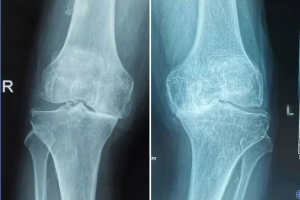

作者供图(膝关节骨性关节炎表现:关节间隙不对称或者变窄,边缘骨质增生和骨赘形成,可见膝内翻畸形)

老寒腿其实就是膝关节骨性关节炎,是一种常见的慢性关节疾病,并不是风湿引起。

特征是膝关节软骨退行性变,包括关节软骨的磨损和关节软骨的变性退化,以及骨质增生等引起的关节疼痛和关节功能障碍。